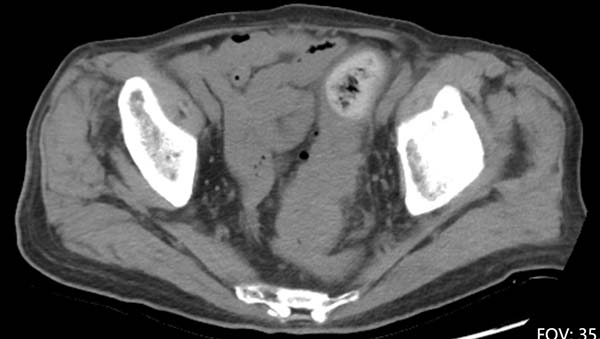

腹盆腔平扫CT显示直肠乙状结肠连接部巨大占位伴周围渗出

近日,93岁的李爷爷(化名)因急性腹痛、便血被紧急送入北京朝阳医院。入院时,老人腹部痛苦难忍。急诊检查结果迅速出炉:直肠乙状结肠交界性恶性肿瘤伴周围渗出,内镜病理回报为中分化腺癌。此时,肿瘤体积较大,患者腹痛症状持续加剧,病情十分危急。摆在医疗团队面前的是两难抉择:保守治疗只能暂时缓解症状,无法根治性切除肿瘤;但为93岁高龄老人实施手术,风险极高,传统开腹手术创伤巨大,术后老人极可能因长期卧床、疼痛应激引发严重并发症,甚至再也无法下床活动。